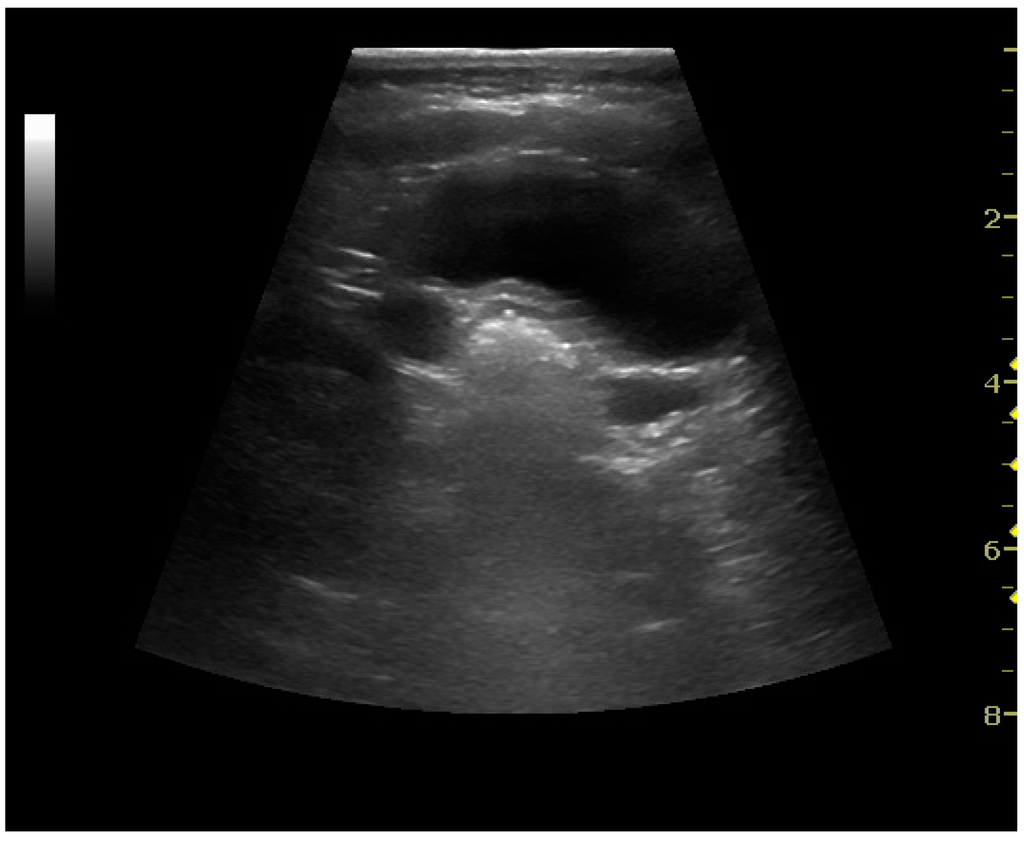

Figure 22. Chronic renal disease caused by glomerulonephritis with increased echogenicity and reduced cortical thickness. Measurement of kidney length on the US image is illustrated by ‘+’ and a dashed line.